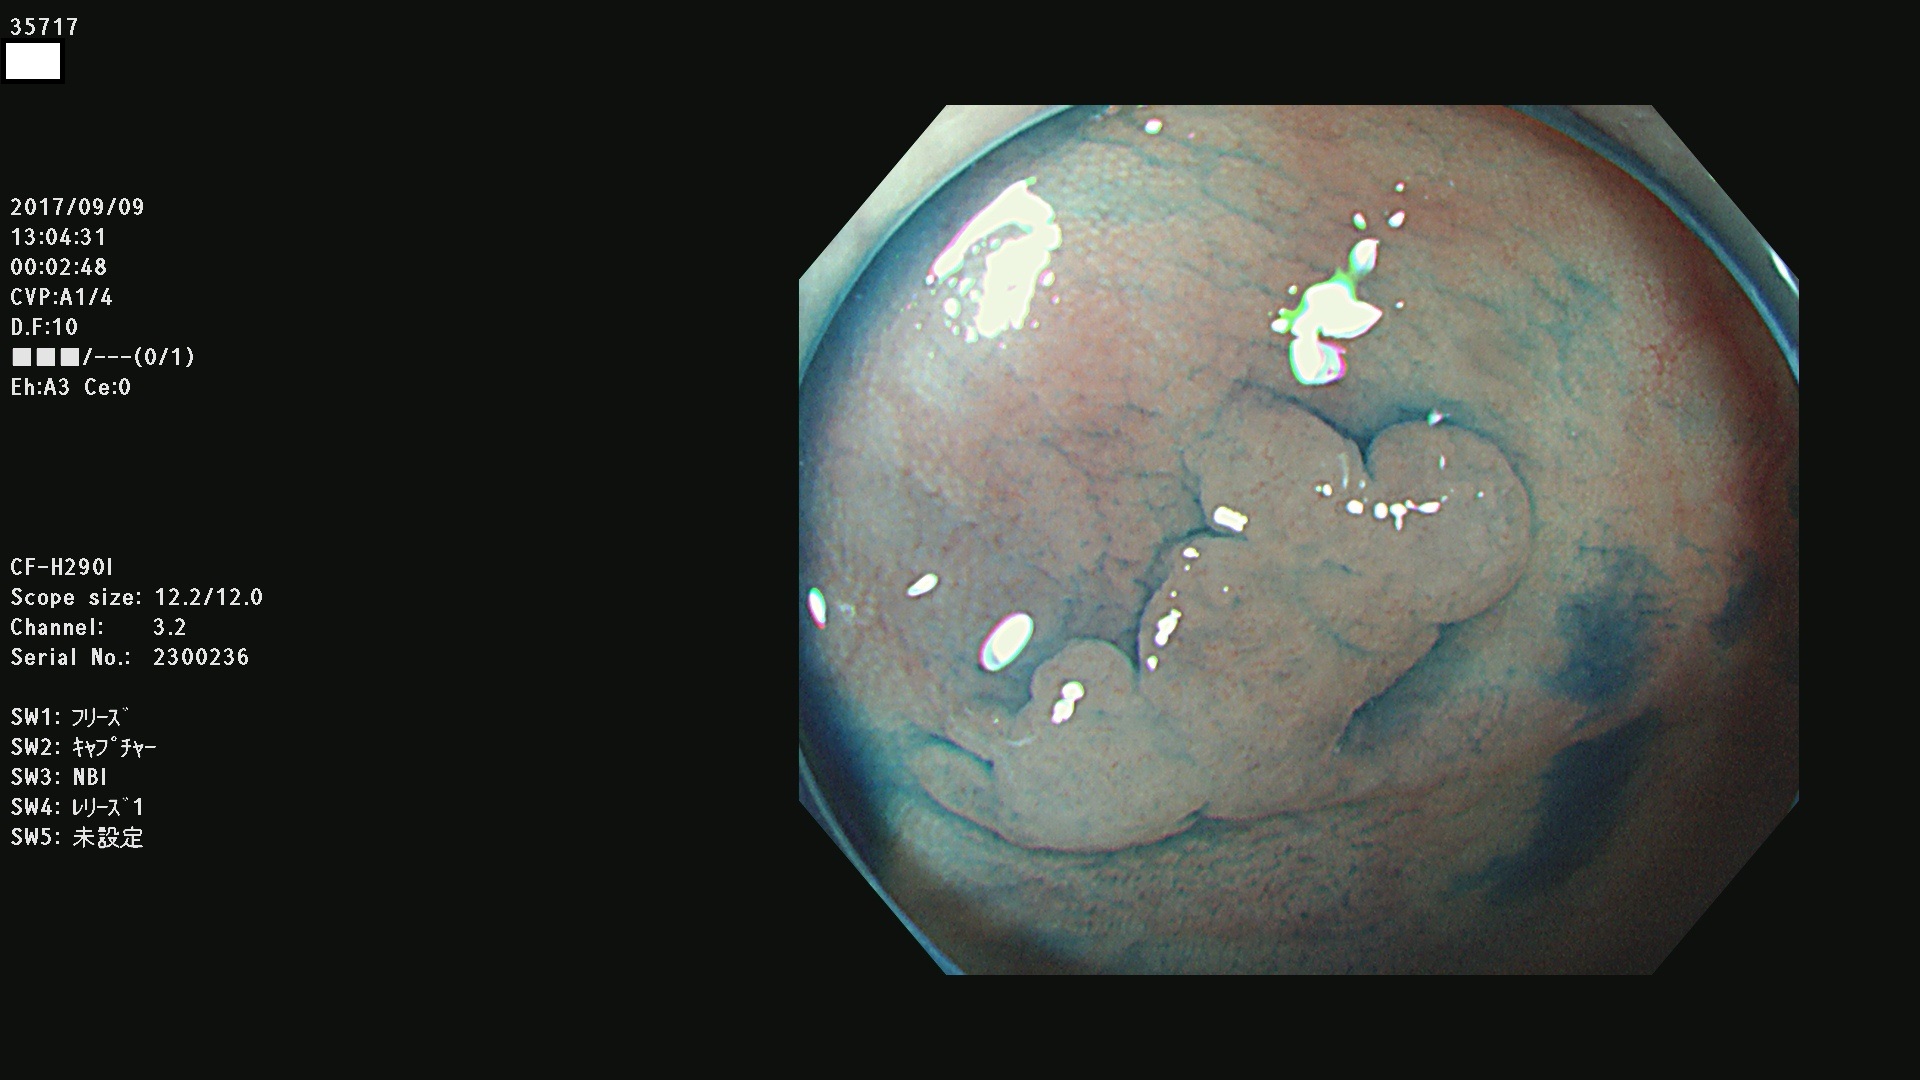

35700 35701 35704 35706 35707 35708 35709 35711(SSA/Pのみ) 35715 35716 35717 35718 35720(SSA/Pのみ) 35722 3576(SSA/Pのみ) 35730 35732 35734(SSA/Pのみ) 35736(SSA/Pのみ) 35741 35742 35743 35744 35746 35748 35749(SSA/Pのみ)35755 35757 35760 35761 35762 35763 35764 35766 35767 35770 35772(SSA/Pのみ) 35773 35781 35783 35785 35786 35787 35788 35791 35795 35796 35797 35798 35799

発見困難で危険性の高い平坦型病変(上記100名より抽出)